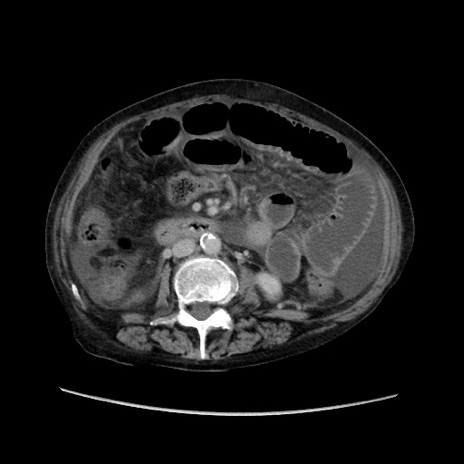

症例31(横断像)

【症例】80歳代 女性

【主訴】腹部膨満感

【現病歴】他院にて肝硬変にてフォロー中。1週間前から便秘、腹部膨満感、臍部腫瘤あり受診となる。

【既往歴】肝硬変

【身体所見】腹部膨隆あり、皮膚変化なし、疼痛なし。

【データ】WBC 4600、CRP 0.25